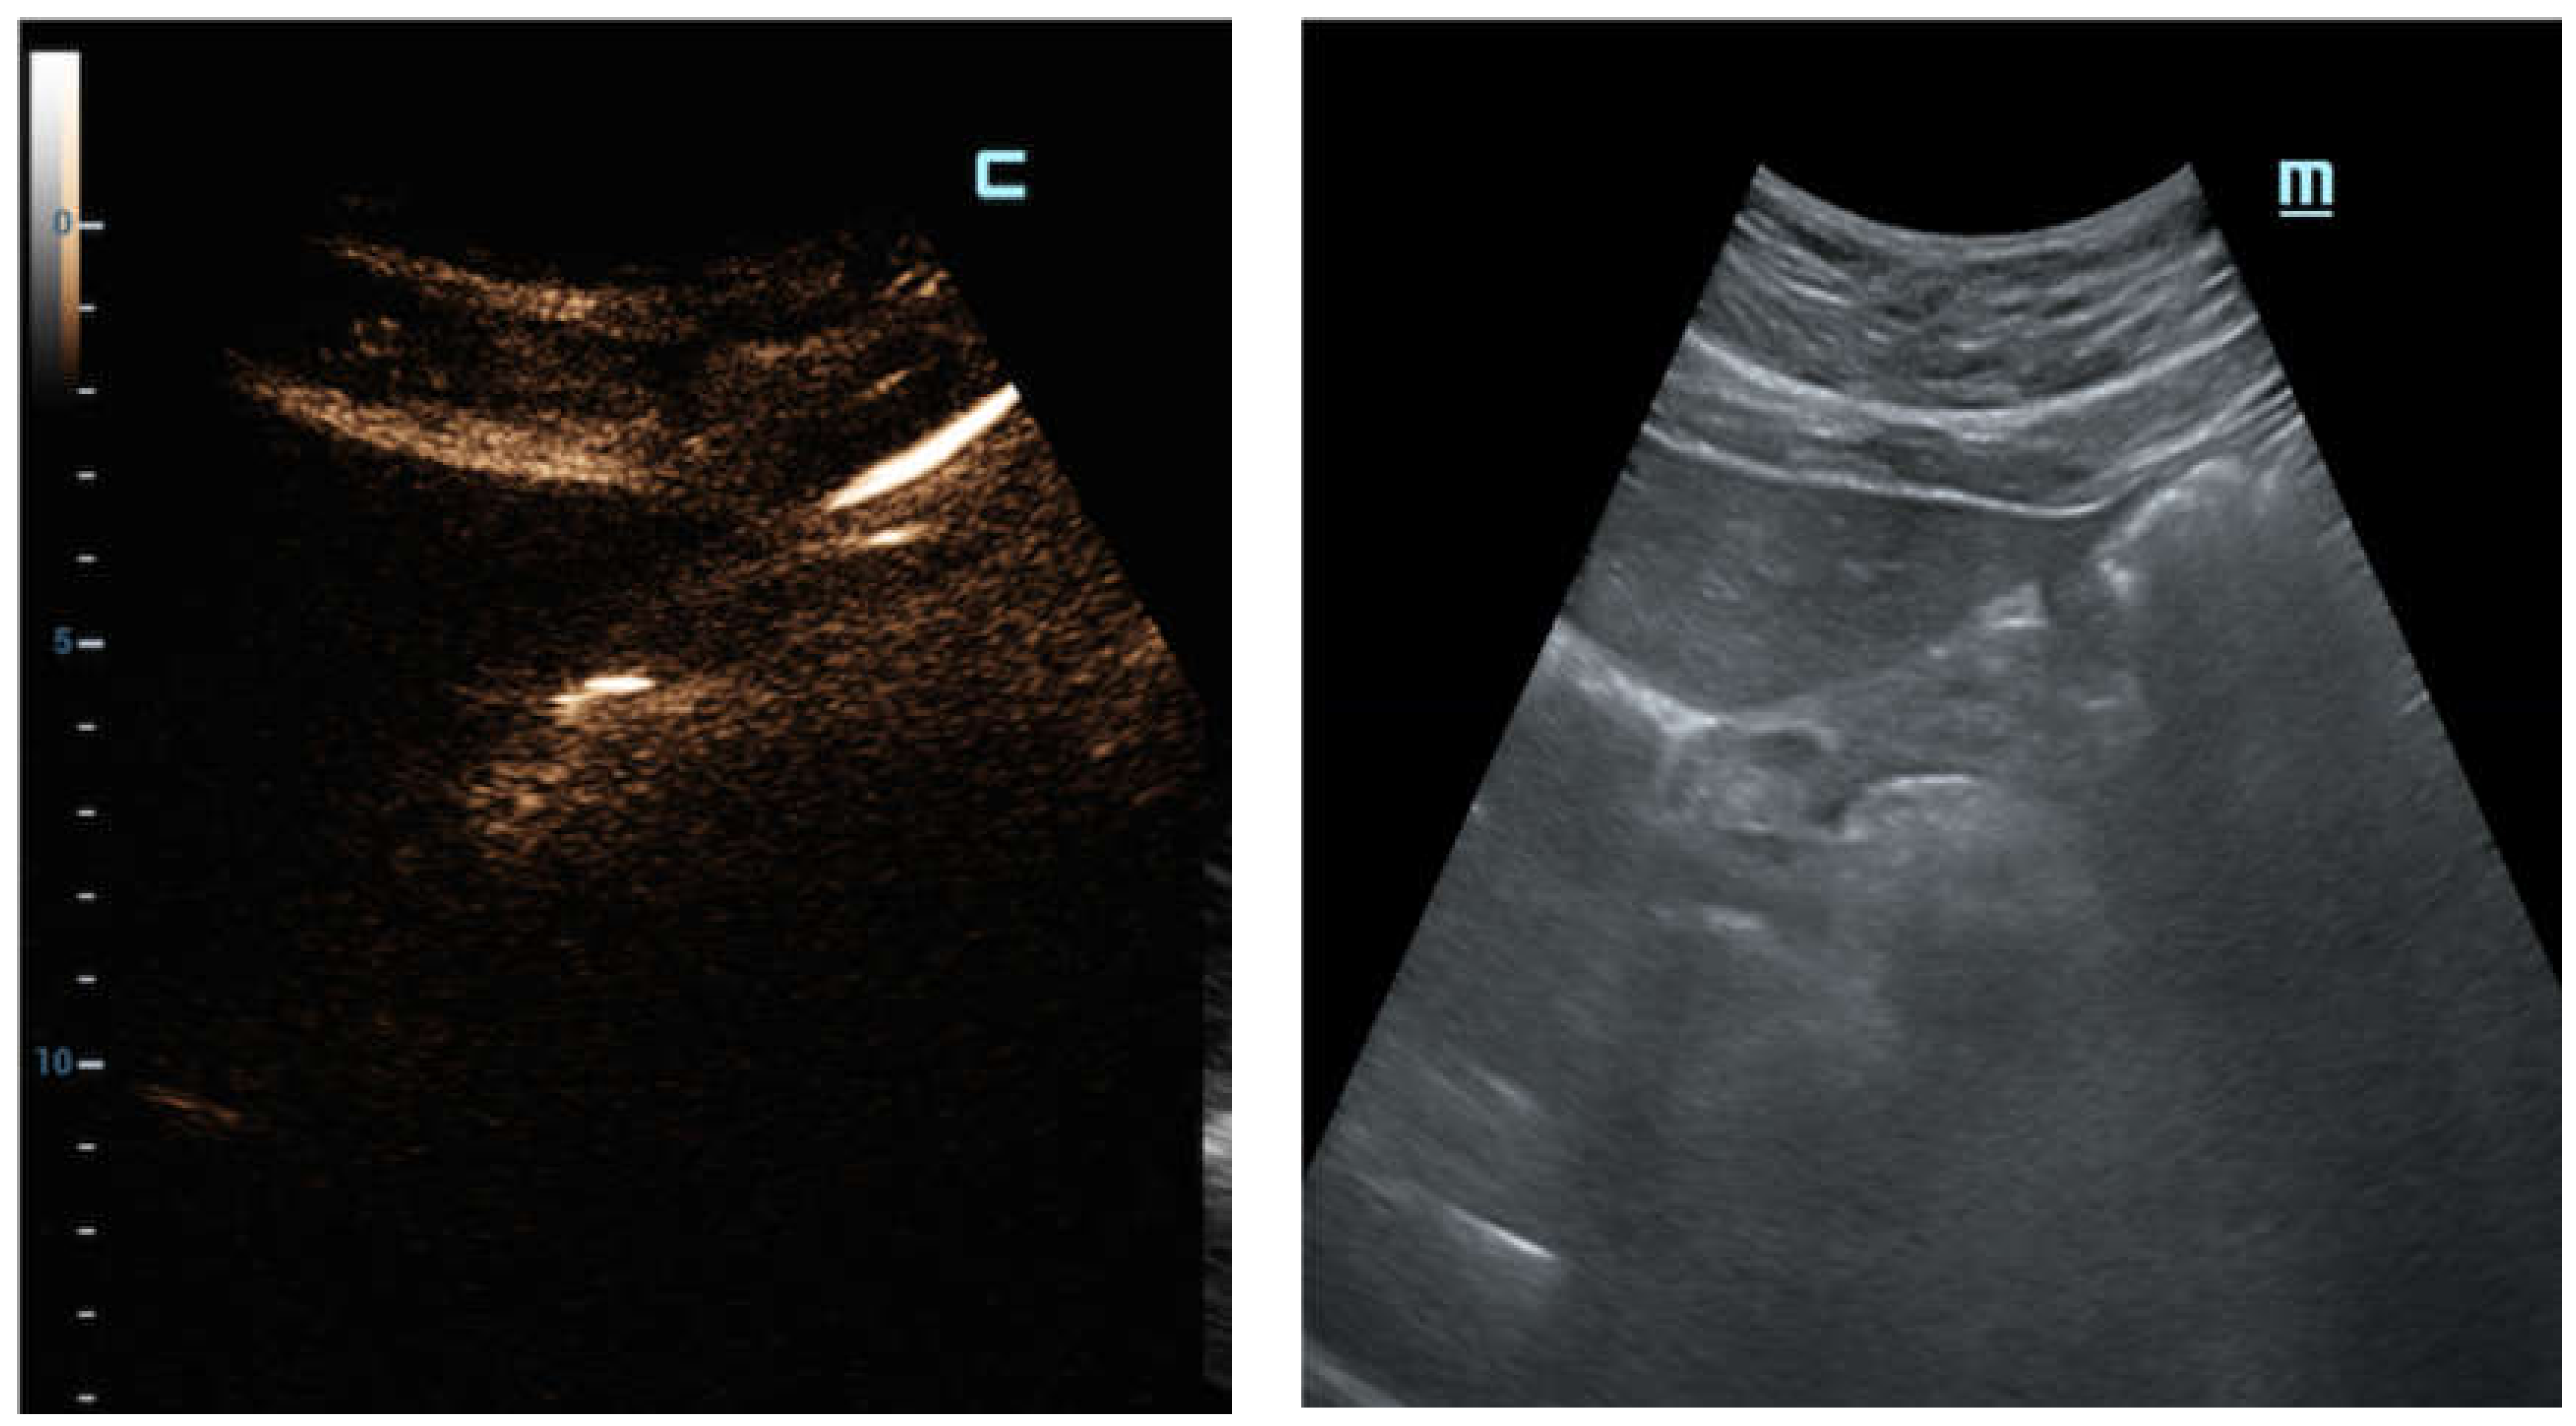

C-mode gave a more intense appearance to the peritoneal stripe when compared to B-mode, identifying the amount of free air, similar to the strongly enhanced peritoneal lines in the pre-hepatic space (

Figure 3), and better enounced the presence of intensely enhanced small amounts of air around the falciform ligament (